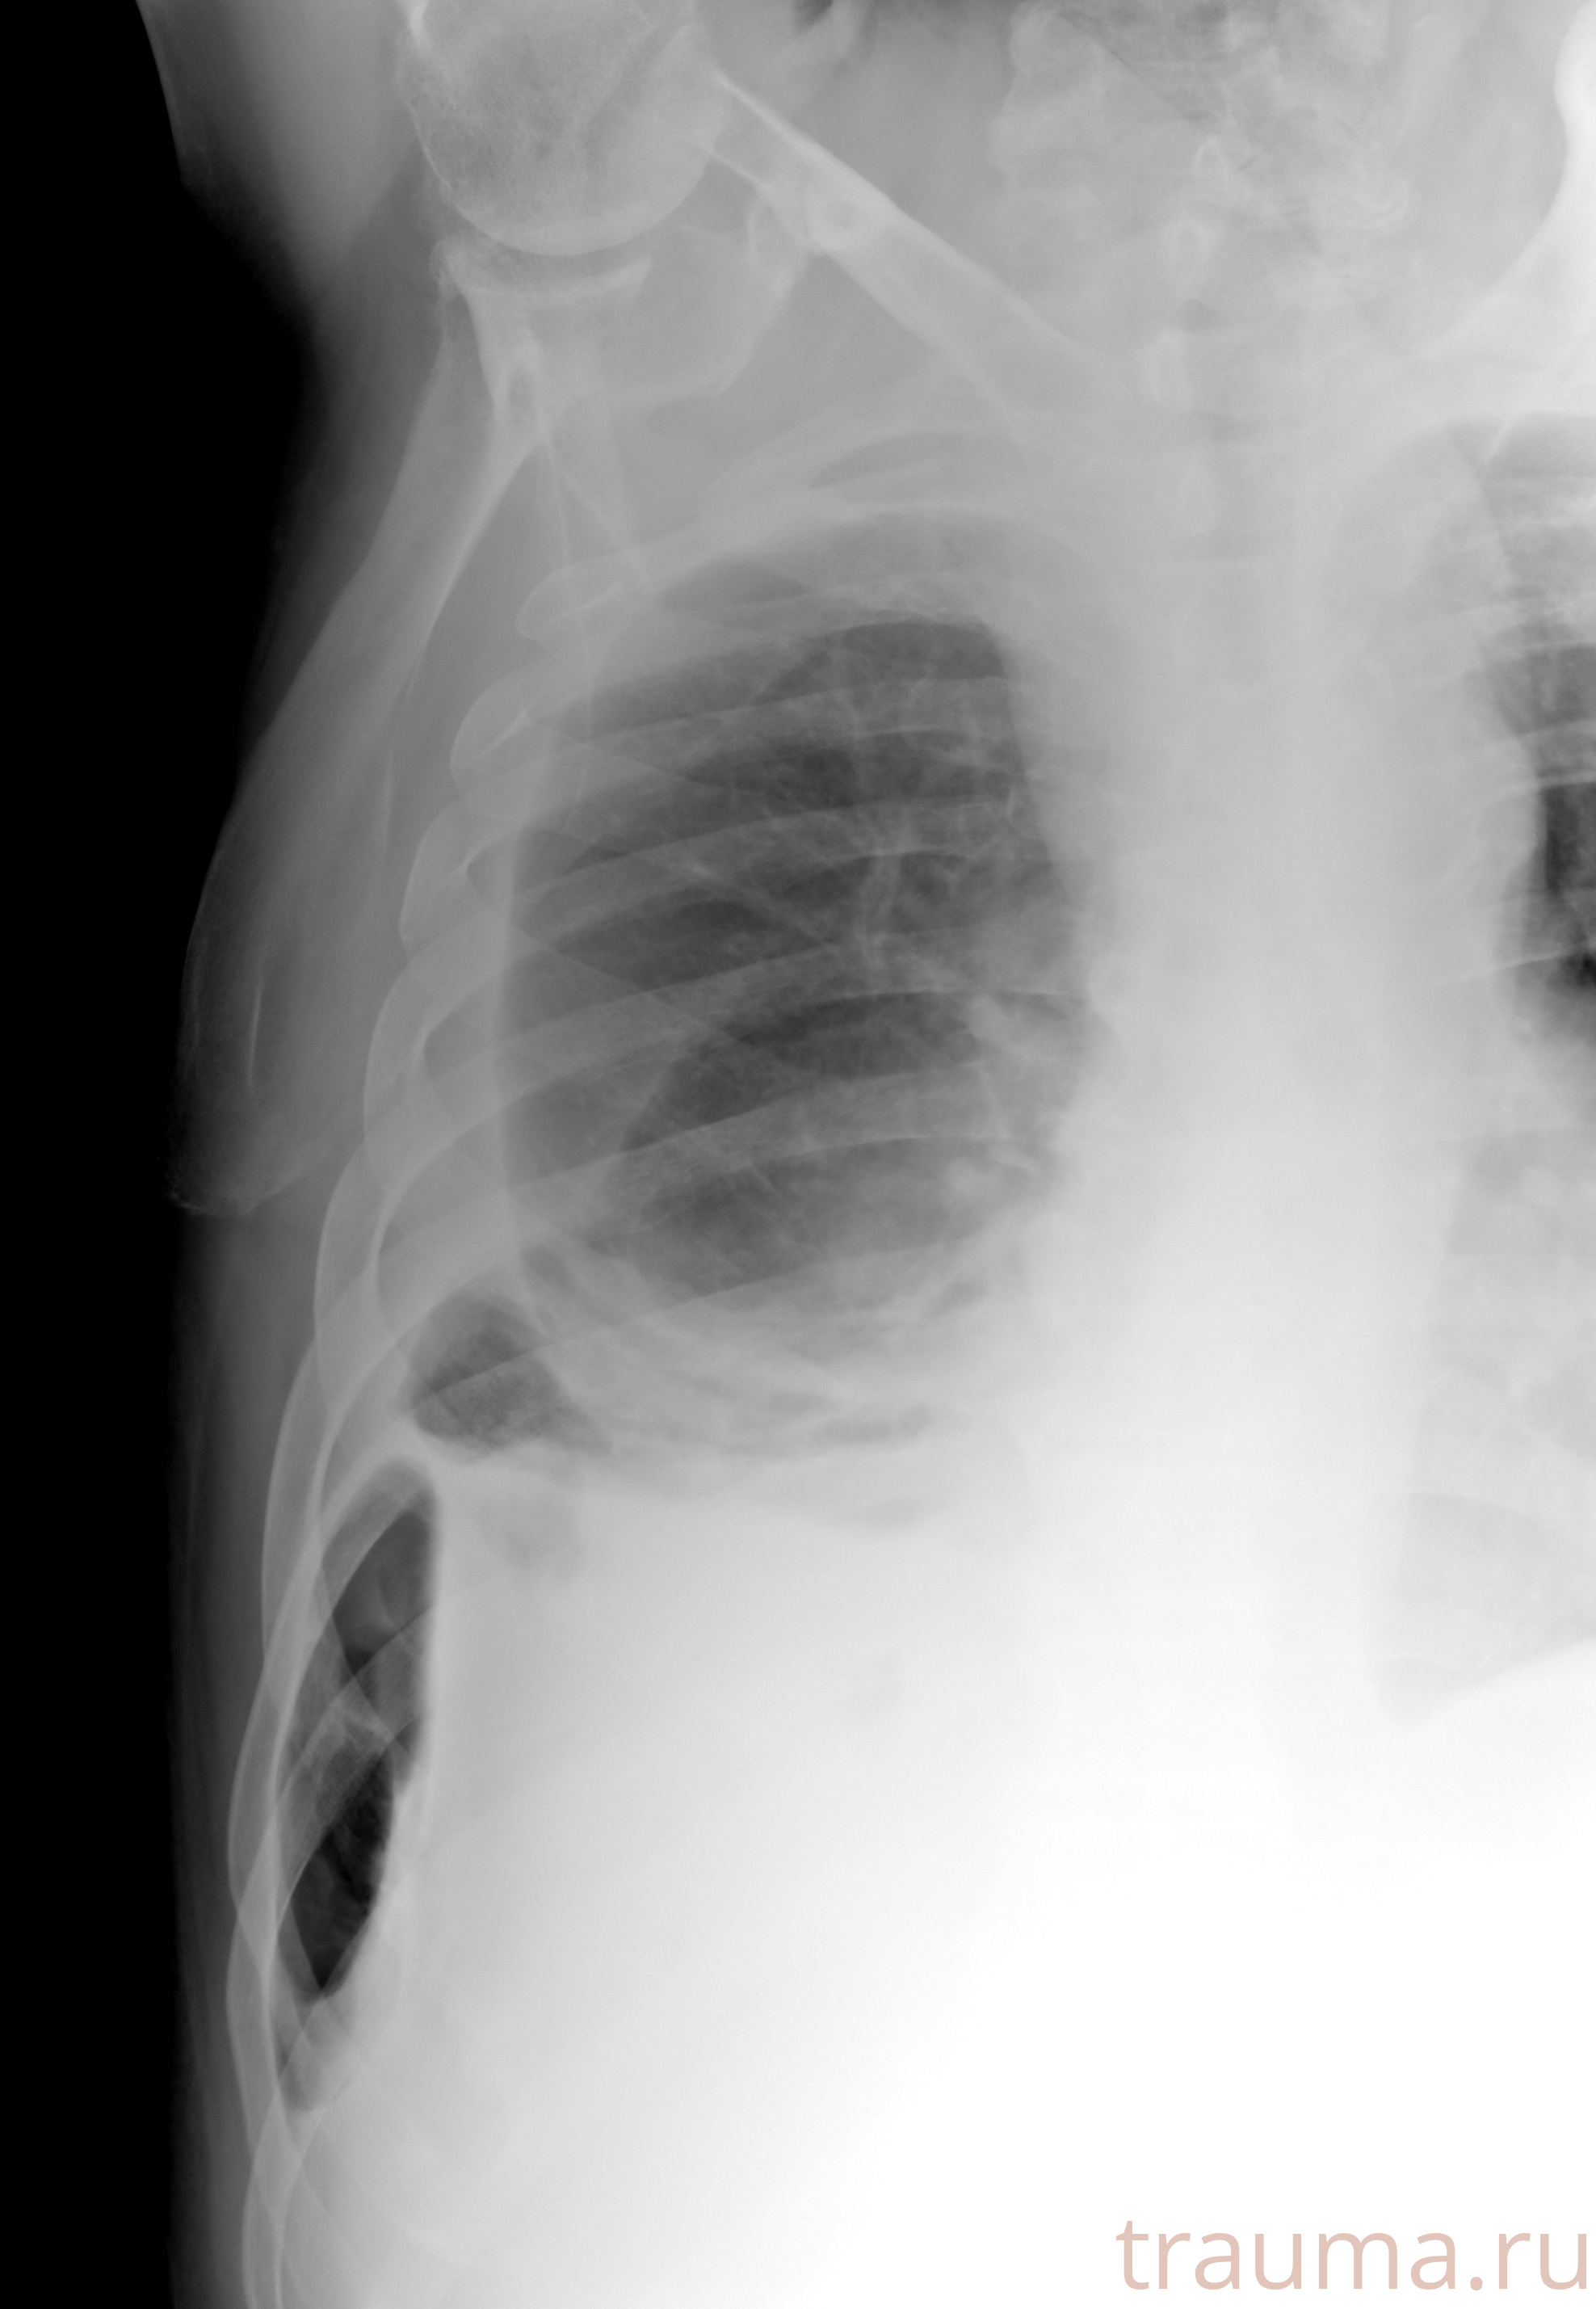

Рентгенограммы

Рентген на дому: по вашему адресу приезжает врач-рентгенолог, травматолог-ортопед с мобильным рентгеновским аппаратом, проводит диагностику травмы или заболевания, делает необходимые рентгенограммы, дает рекомендации по дальнейшему лечению. Получить качественные снимки в домашних условиях возможно благодаря уникальной методике, разработанной МосРентген Центром для института  Склифосовского